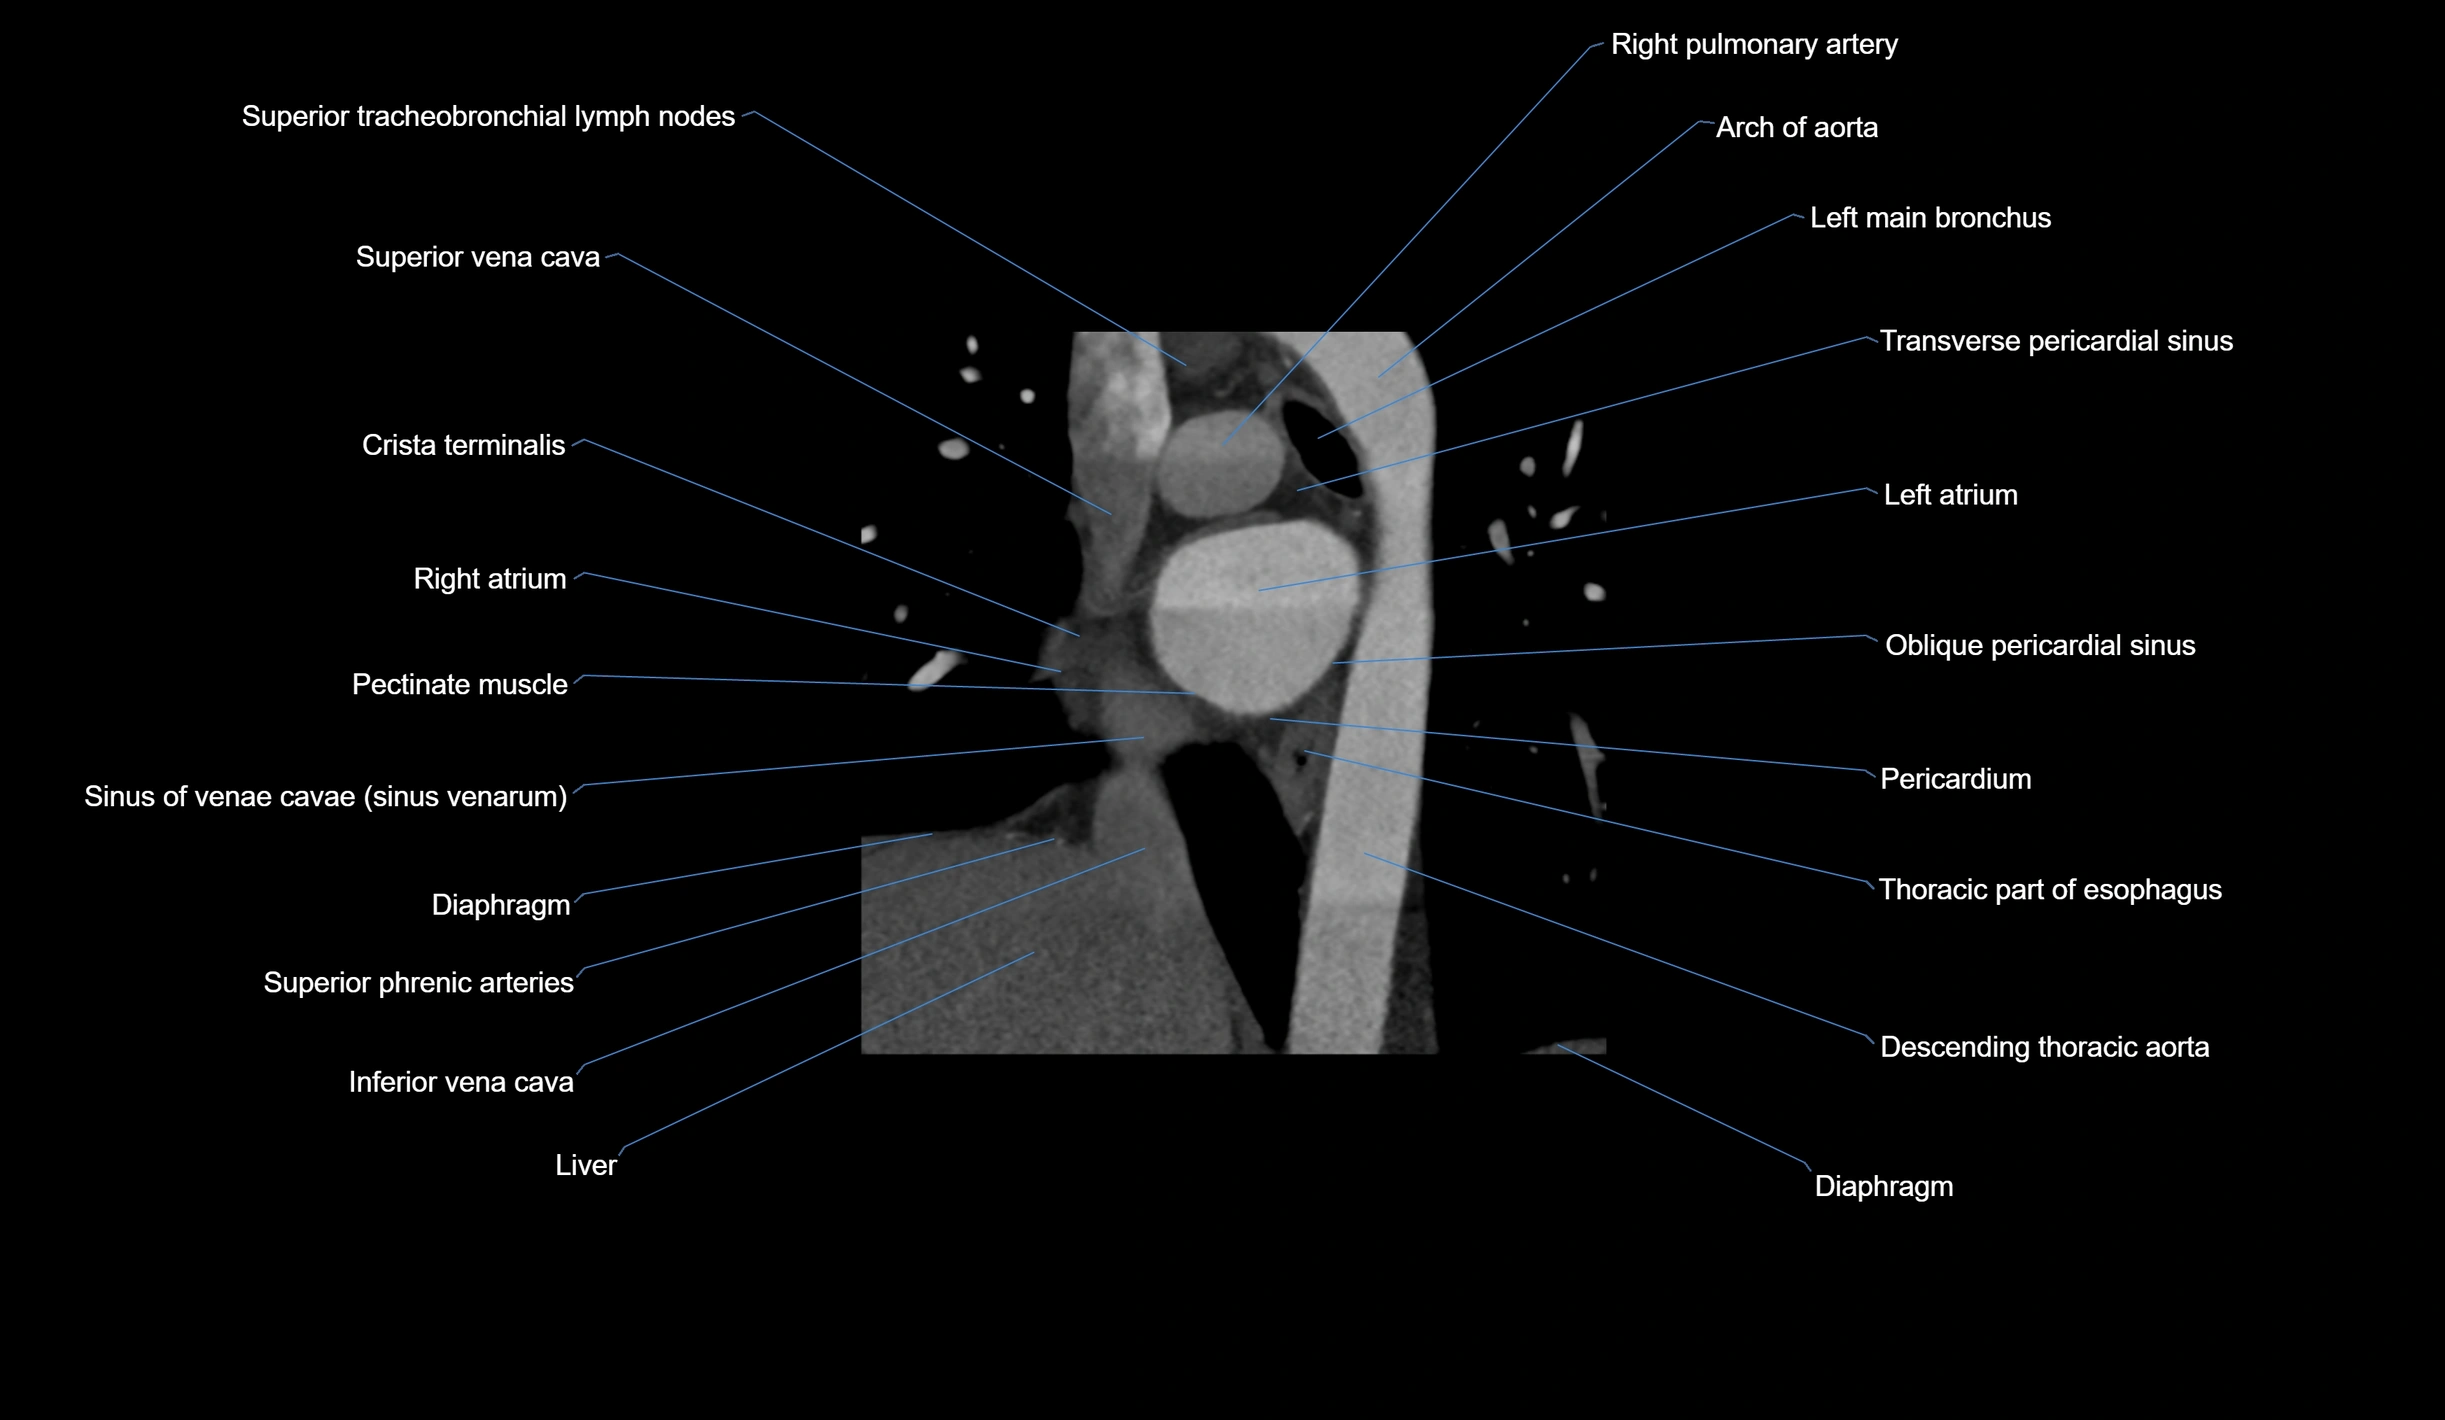

CT Appearance

Non-contrast CT (Calcium Scoring):

-

AM artery visualized for coronary calcium scoring

Calcified plaques appear as hyperdense foci; scored with Agatston method

CT Coronary Angiography (CCTA):

Best non-invasive modality for acute marginal artery visualization

Shows origin, course along the acute margin, and right ventricular branches

Detects stenosis, occlusion, calcified and non-calcified plaques, aneurysm, or anomalous course

Multiplanar reformats and 3D reconstructions help in pre-PCI and surgical planning

Critical for assessing right ventricular infarction risk in RCA disease

MRI image

CT images